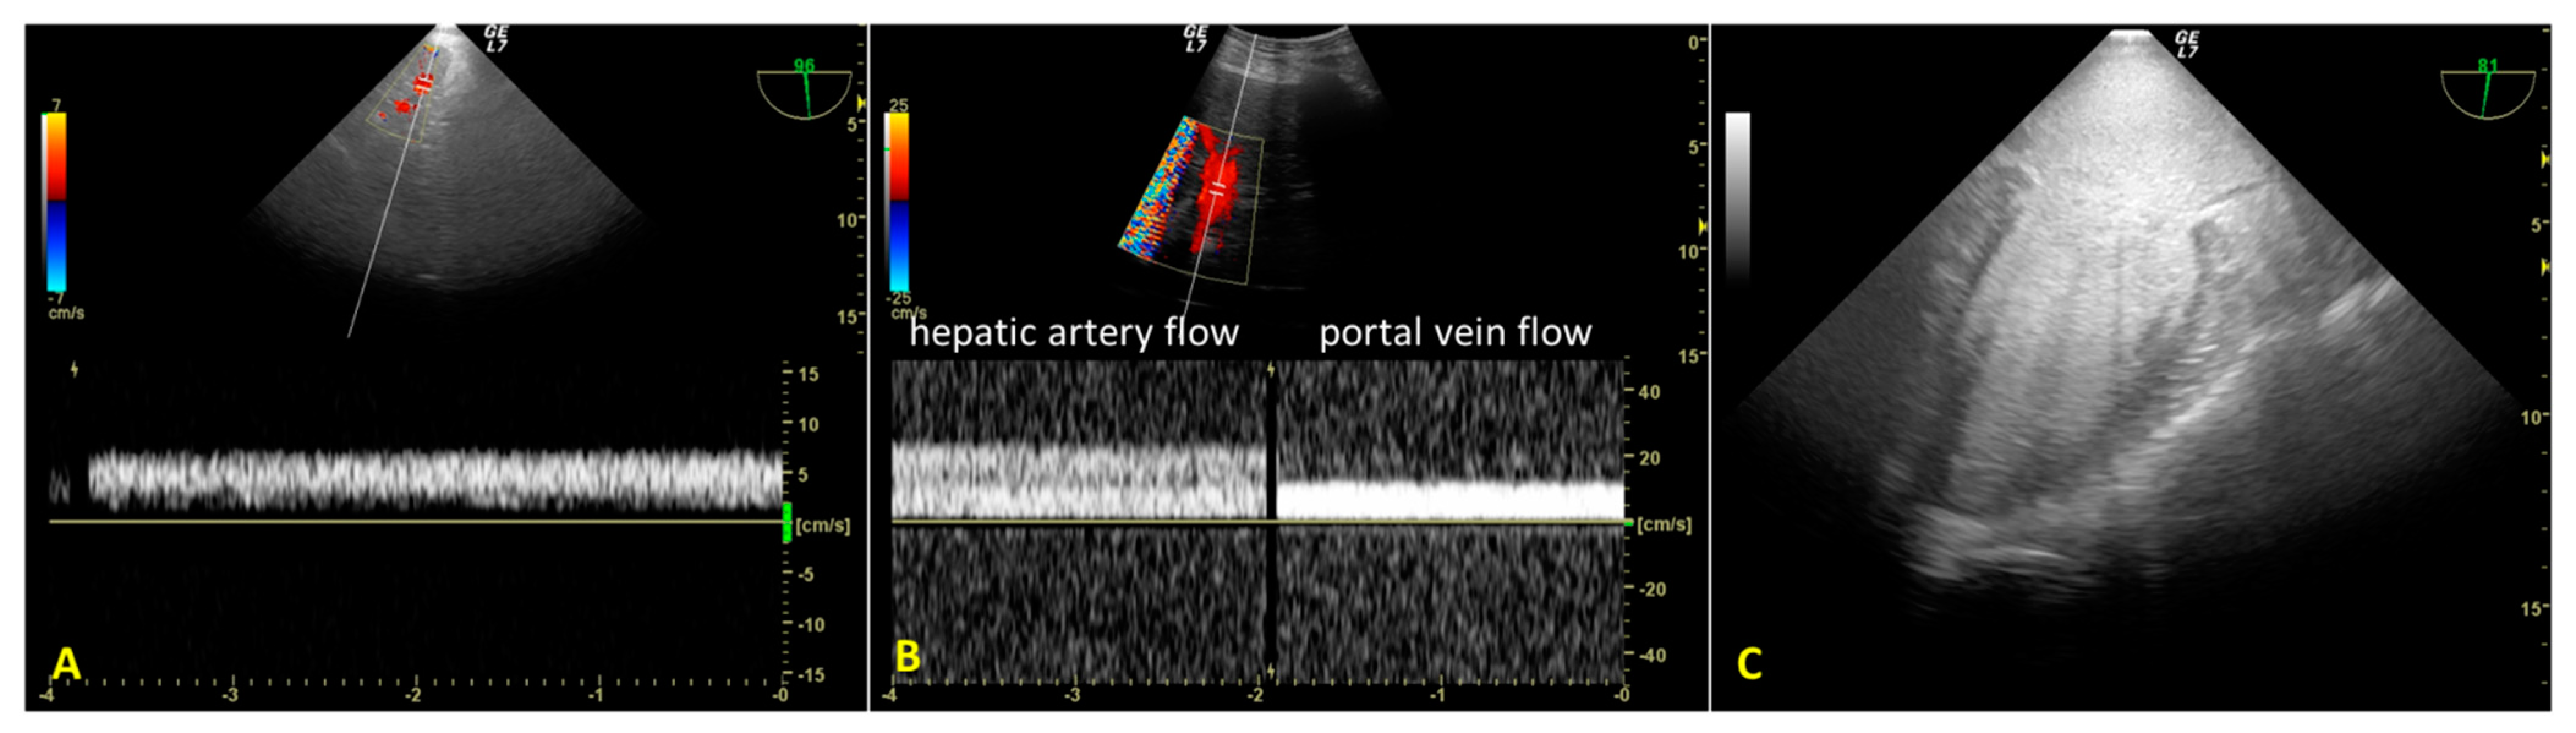

During A-NRP, we monitored hepatic re-perfusion with color Doppler US and laboratory tests. TEE revealed initial reduced hepatic artery blood flow (transgastric view) due to incomplete aortic occlusion and decreased hepatic perfusion pressure (Figure 3A). After complete aortic occlusion, hepatic artery blood velocity increased, and portal vein blood flow was sampleable. (Figure 3B) At the same time, blood lactates decreased from 9.4 mEq/L to 5.2 mEq/L. TEE also allowed us to observe the absence of blood flow in the left ventricle and atrium after complete aortic occlusion, as well as the lack of cardiac contractility, despite PM activity displayed on the electrocardiogram (Figure 3C).

In our case study, TEE and percutaneous abdominal US helped verify the efficiency of A-NRP by assessing abdominal organ perfusion. The reduced blood flow velocity in the hepatic artery and the inability to sample the portal vein blood flow (as well as a reduced MAP) indicated hepatic hypoperfusion. Using TEE, we looked for the cause of the hypoperfusion, identified it as incomplete aortic occlusion, and we corrected it (unfortunately, there is currently no standard limit for blood flow velocity during A-NRP and more studies are needed to verify the impact of mean blood flow velocity on recovery of organ function).

Figure 3. (A). Transesophageal color Doppler echocardiography with transgastric approach during the initial phase of regional extracorporeal support. Slow hepatic artery flow is sampled due to incomplete aortic occlusion (continuous right hepatic artery flow velocity = 7 cm/s). Portal vein flow was absent. (B). Color Doppler ultrasound with convex probe after complete aortic occlusion. Right hepatic artery flow was increased (velocity 25 cm/s) and the portal flow was sampled (velocity 12 cm/s). (C). Absence of flow in the left ventricle and atrium after complete aortic occlusion (mid-esophageal two-chamber view).